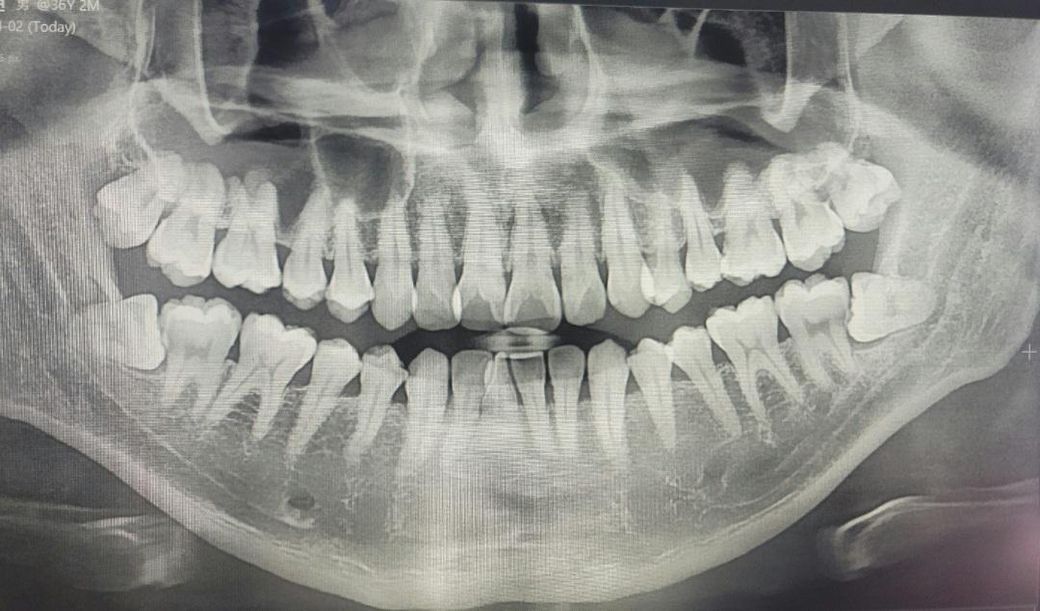

스케일링 하러 가면서 엑스레이를 찍으니 아래 누워있는 사랑니 때매 그 앞 치아 충치가 작년보다 더 진행됬다고 치아를 발치 해야될수도 있고

살리려면 대학병원이나 전자 현미경? 있는 치과에 가서 치료를 해야 될수도 있다 하시는데

제 엑스레이를 한번 봐주시고 의견 남겨주시면 감사하겠습니다

파노라마상에서 사랑니 옆 충치가 의심되는 상황이긴 합니다

일단 사랑니 빼고 그 옆 치아 상태 봐야 합니다